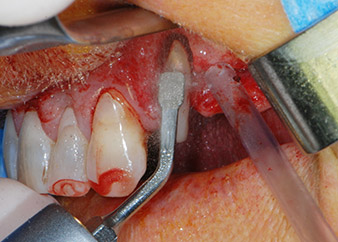

Въпреки това, ние се придържахме към първоначалния си план да запазим и двата зъба като абатмънти за временен мост по време на 6-месечната остеоинтеграция на имплантите. При повторна интервенция, ситуацията трябва да се преразгледа. Първо, в опит да се овладее ендо-перио проблема, останалата повърхност на зъба е внимателно обработена с пиезохирургично оборудване (Piezomed, W&H, използван с накрайник S1 под формата на шпатула, първоначално проектиран за ерозия на латералната синусна стена) (Фиг. 4).

След това апексът се изпилява със същия инструмент, за да се отстрани остатъчната инфектирана апикална тъкан и да се намали възможното допълнително усложнение по кореновите канали (апикоектомия) (Фиг. 5). Ретроградно запълване не е необходимо, защото ортоградното запълване току-що е ревизиран.

Преди поставянето на импланта, инфектираната тъкан е отстранена от алвеоларната кост в имплантното ложе и около зъба-абатмънт с накрайник, проектиран за оформяне на костта и събиране на костни блокове (Piezomed, накрайник B5) (Фиг. 6 и 7).